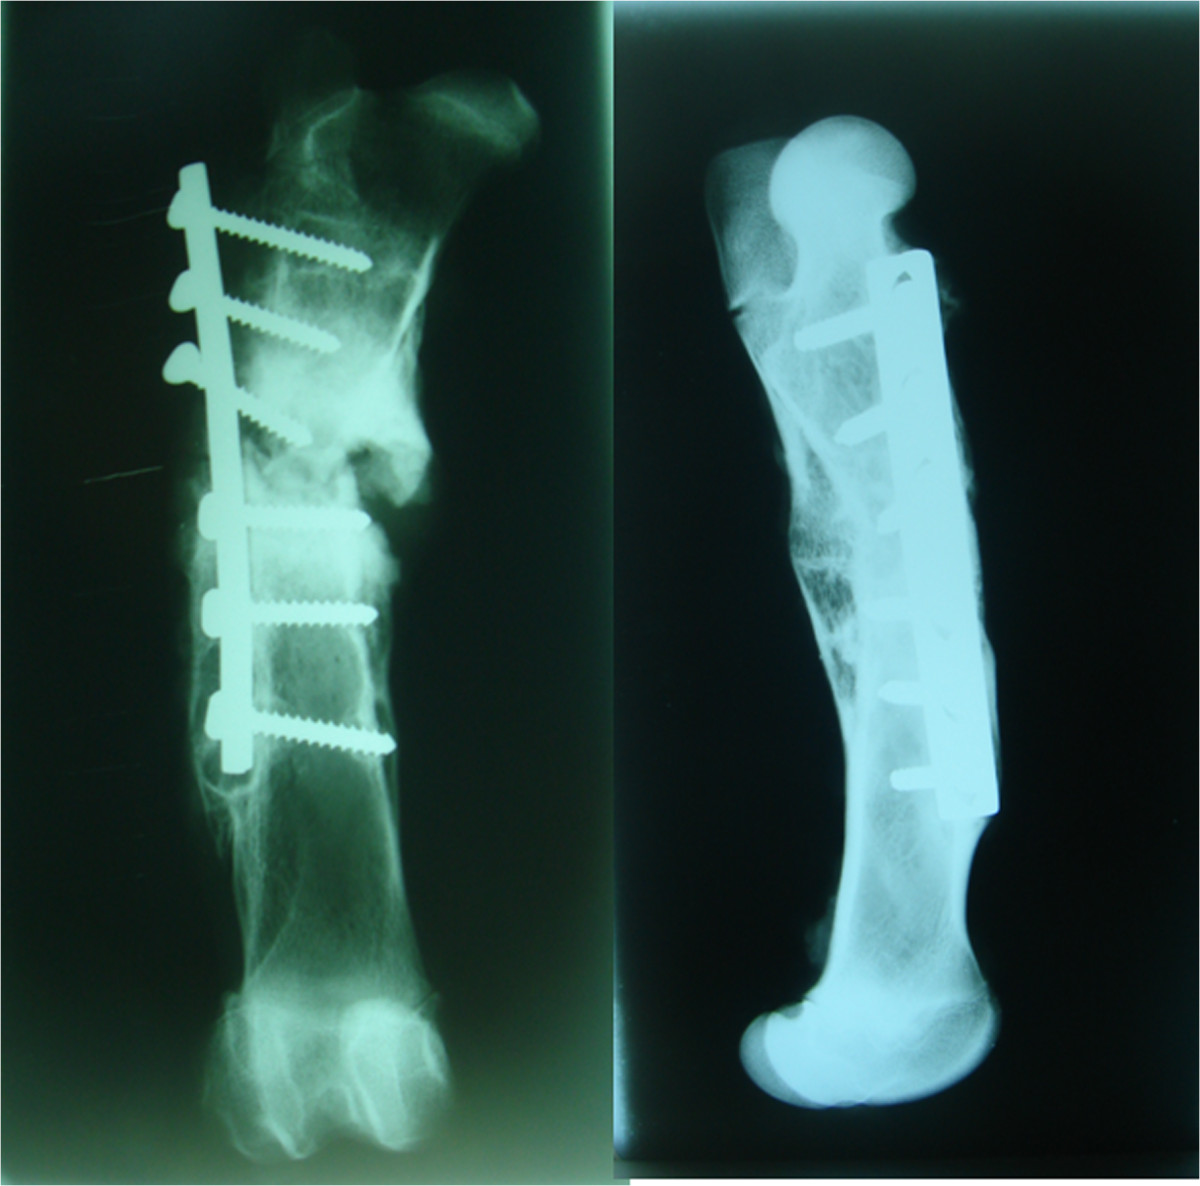

Figure 4.

Two examples of complications in animals operated on without SLE after 16 weeks: absence of consolidation and loosening of all proximal screws on the left and approximately 30° of femoral recurvatum on the right.